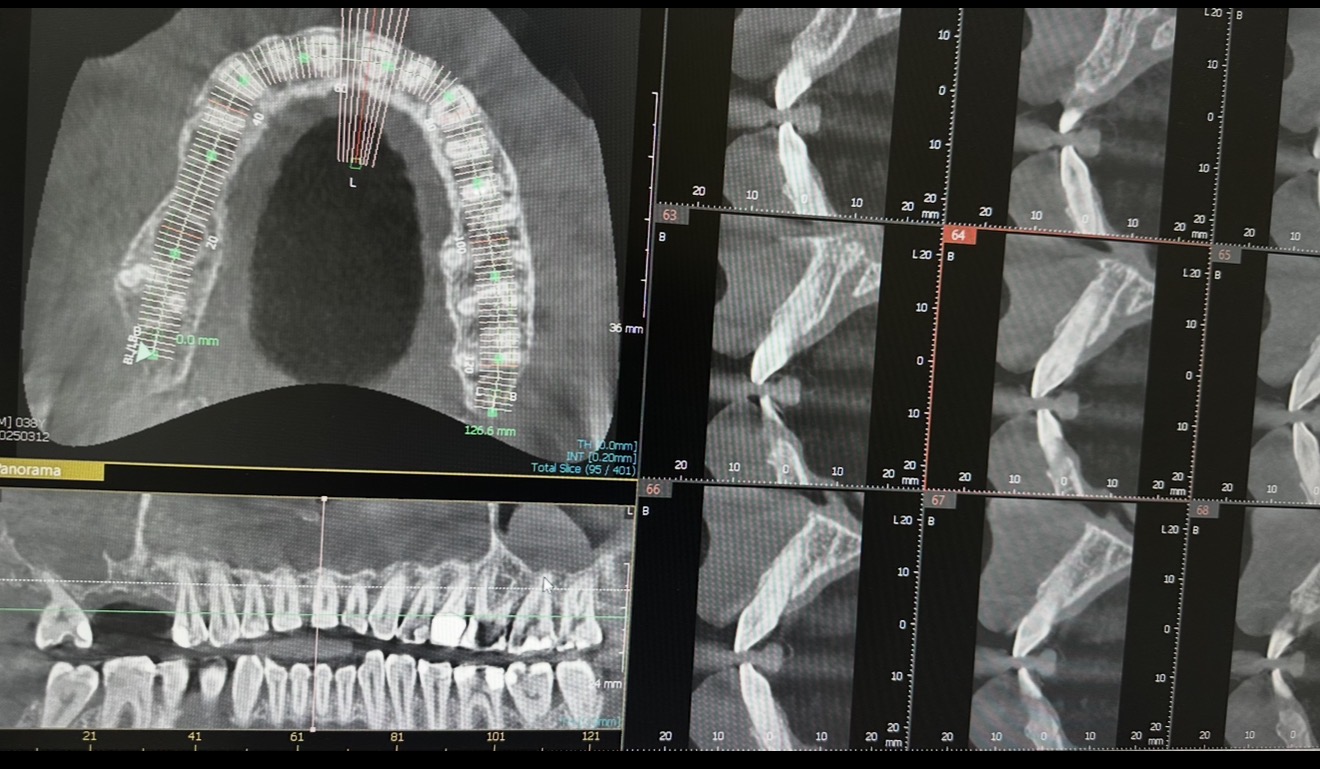

Per diagnosi più rapide, minimizzando il dolore ottimizzando i risultati, come Scanner intraorale e apparecchiature di radiografia digitale.